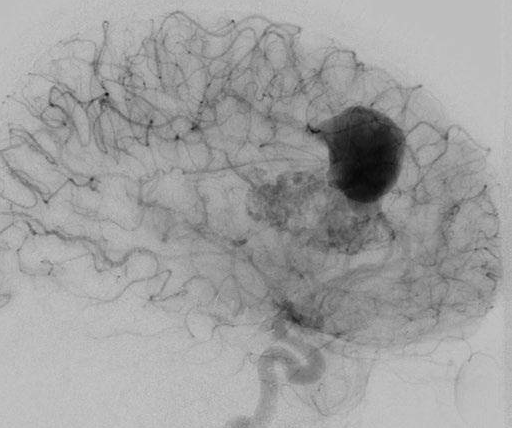

他紧急行半侧颅骨切除术,随后血管造影显示右侧动脉瘤,AVM由双侧PcaA供血,引流向前MedFrV和SplenV【左侧ICA像,(a)前后位(b)侧位】(c)首先通过双侧开颅并排夹闭动脉瘤(鼻朝右,中线呈水平,重力牵开右侧额叶),然后切开动脉瘤使之缩小。

患者案例2:17岁男孩,表现为来自于右侧胼胝体压部AVM的脑室内出血(补充Spetzler-Martin分级4级:S1V1E1/A1B0C0),SplenA供血,SplenV和内侧AtrV引流右椎动脉造影。